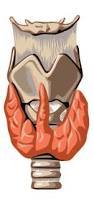

thyroid gland:

right lobe

left lobe

isthmus

pyramidal lobe